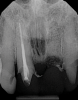

(11.) A pathosis apical to the maxillary central incisors was initially not diagnosed after evaluating the periapical film; however, the CBCT image revealed its presence. Only using the CBCT image could it be determined that the lesion was not odontogenic in origin and that it did not involve the nasopalatine foramen. This diagnosis was supported by a referral to an oral and maxillofacial radiologist.

Figure 11

(12.) A pathosis apical to the maxillary central incisors was initially not diagnosed after evaluating the periapical film; however, the CBCT image revealed its presence. Only using the CBCT image could it be determined that the lesion was not odontogenic in origin and that it did not involve the nasopalatine foramen. This diagnosis was supported by a referral to an oral and maxillofacial radiologist.

Figure 12

Are most or all dentists qualified to read CBCT images? Although the technology can be intimidating to clinicians who are not experienced in its use, the truth of the matter is that it is easier to identify structures and pathoses in CBCT images than in any 2D radiograph. This is made clear by the ability of patients to see and understand the images presented to them without receiving any formal training whatsoever. Because all dentists are trained in radiology, they can easily read a radiographic image created by a cone beam. The real issue for clinicians involves mastery of the software that their particular CBCT unit uses so that they can manipulate the images and best visualize the area in question.9 To this end, the education and training provided by the manufacturers of CBCT units can be very helpful to clinicians before they are able to gain experience through multiple evaluations of images (Figure 11 and Figure 12).

Because CBCT scans provide so much information, some clinicians question the limits of what they are responsible for diagnosing. That is the wrong question to be asking. All dentists are responsible for the diagnosis of any condition in the oral cavity. The correct question that these clinicians need to be asking is what exactly are they missing on their 2D radiographs that they are unaware of but just as responsible for? With CBCT, the clinician misses less, diagnoses more accurately, and can present all of the conditions to the patient instead of just addressing his or her chief complaint. In situations where a CBCT scan is acquired and no pathosis is noted, when the clinician pronounces the patient healthy, he or she will be more accurate in that diagnosis as well.